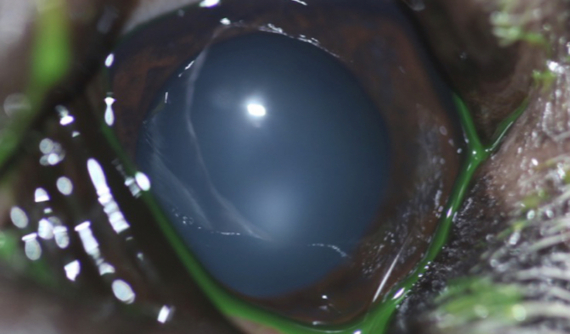

Brutus mostraba un crecimiento irregular sobre la superficie de su ojo derecho.

Tras la exploración oftalmológica completa realizamos una OCT de córnea y una ecografía UBM para valorar apropiadamente la masa y su profundidad.

El resultado de la biopsia fue de carcinoma de células escamosas in situ.